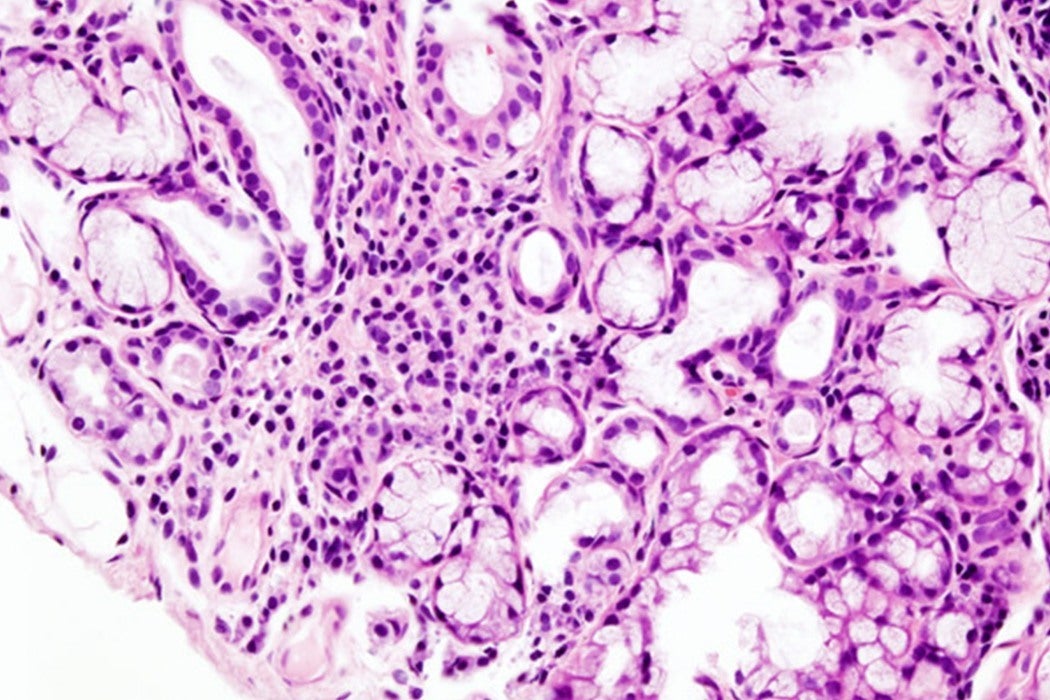

In our cells, calcium is stored in a network of tubule-looking structures where proteins are synthesized, called the endoplasmic reticulum (ER). Signals can trigger the release of calcium from the ER into the cell itself, which can then cause saliva and other secretions to be released out of the cell. To get from inside the ER to the outside, calcium passes through what’s called an IP3 receptor. These IP3 receptors are complex, and are made of four units, all of which work in conjunction to let calcium flow out of their reserves.